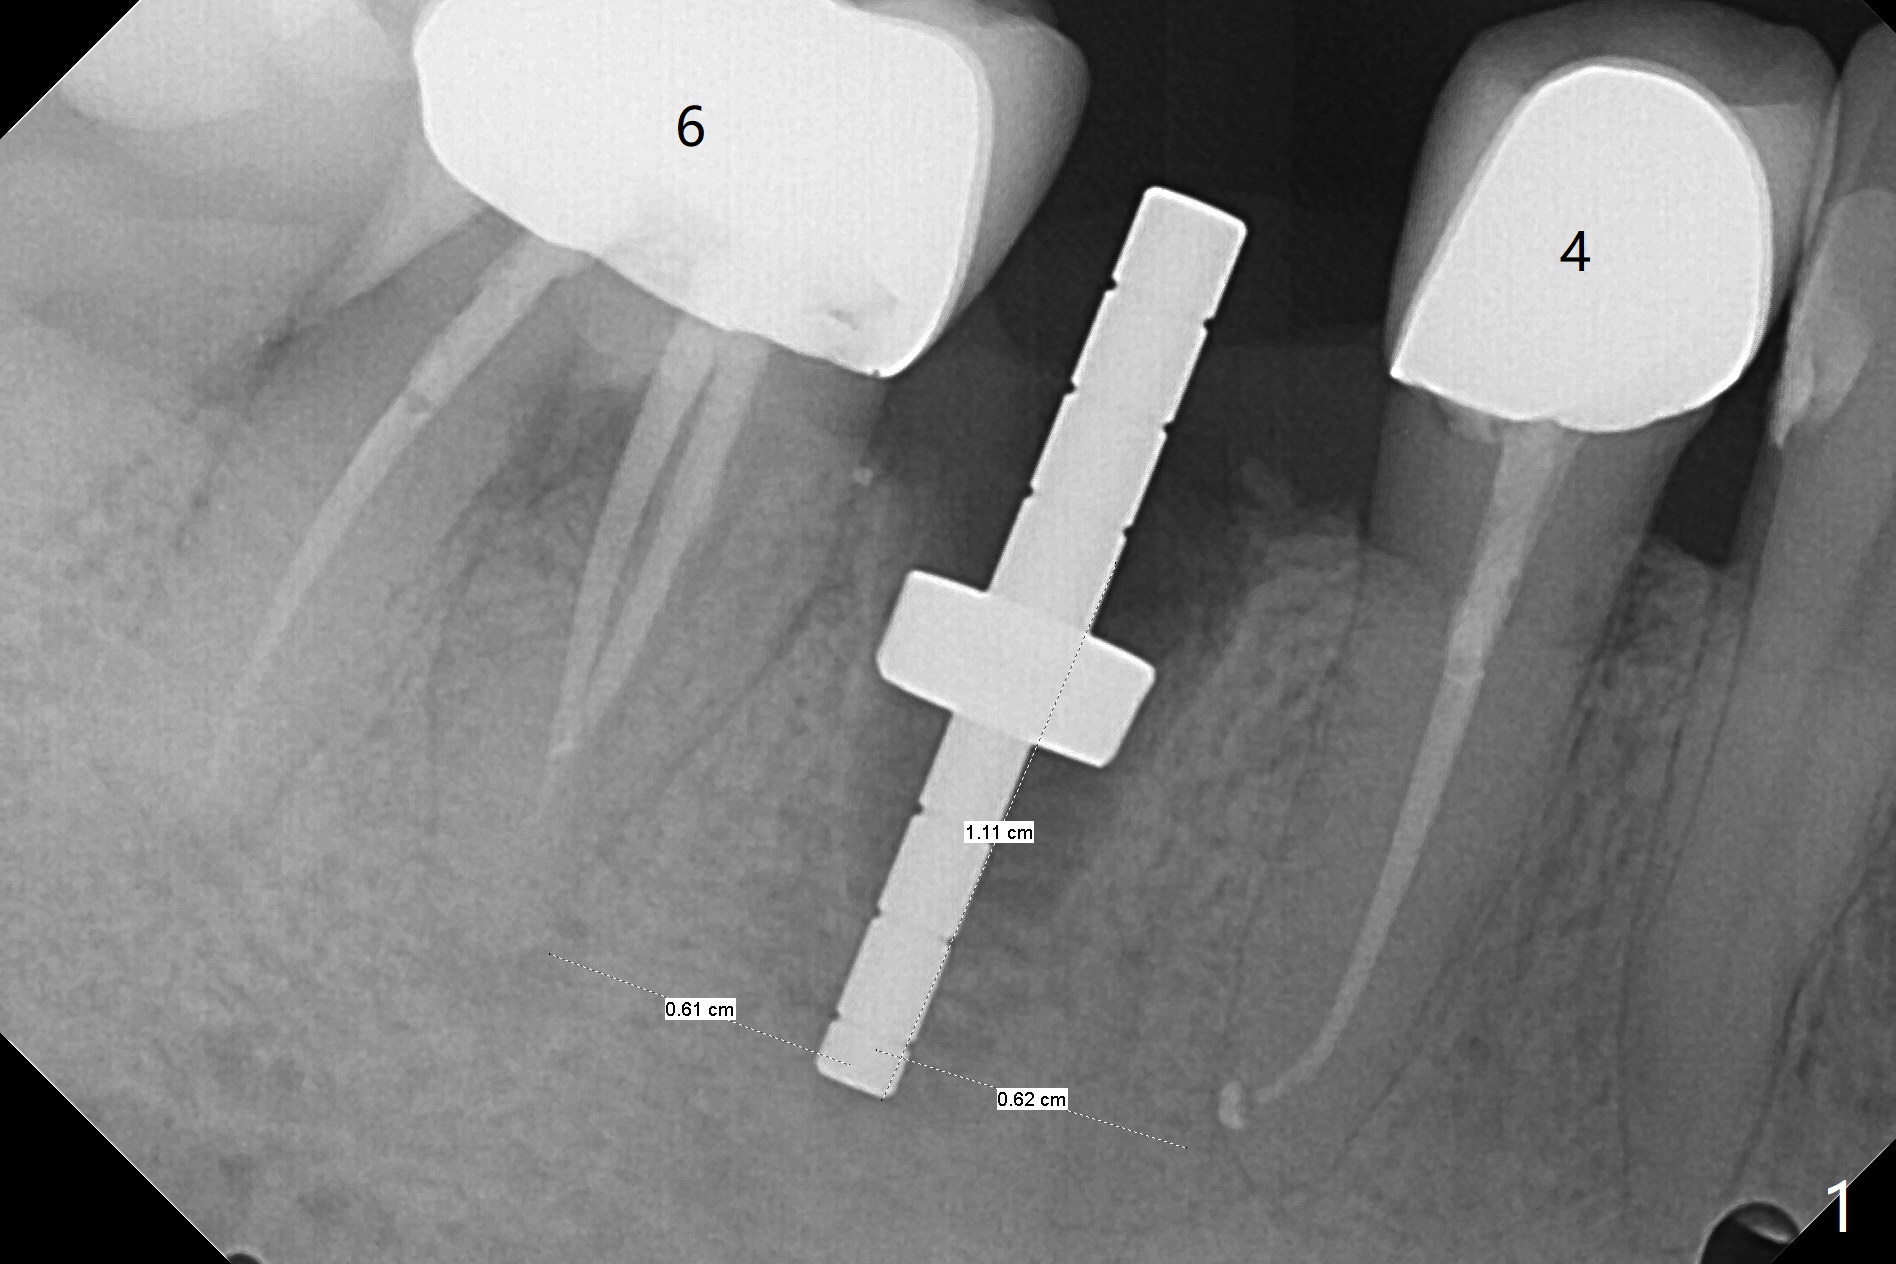

为了准确,这个病例徒手种植需要拍摄8张X光片(这里仅显示其中4张,图一至四),如果采纳导板,2张足够了,而且不担忧神经损伤问题。